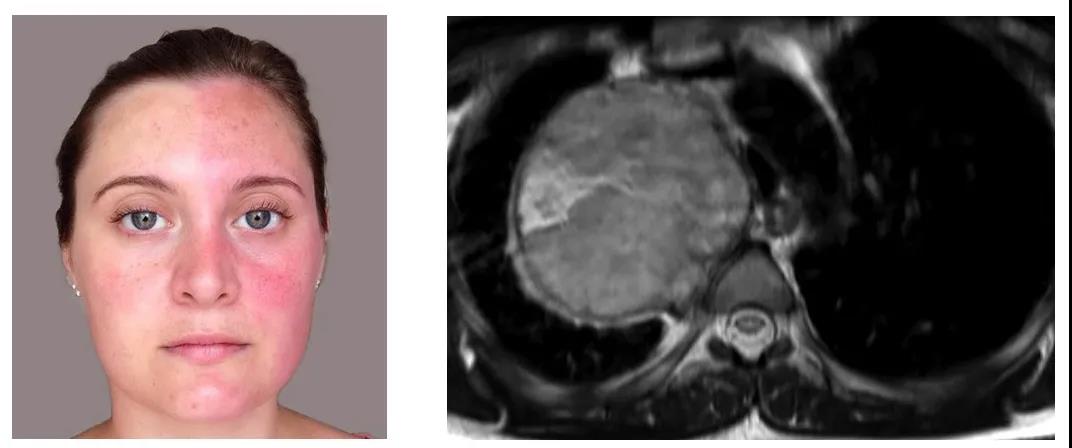

2015 年 BMJ 杂志将一位剧烈运动后一侧面部潮红、对侧少汗的 28 岁女性带入我们的视野。

该女性患者无呼吸系统症状,因拍摄胸片偶然发现「右肺尖」不明占位,才引发患者就诊求医。随后进行的 MRI 提示右肺尖神经鞘肿瘤,手术切除后的组织学病理证实是雪旺氏细胞瘤(Schwannoma)。术后患者的症状显著缓解 [1]。